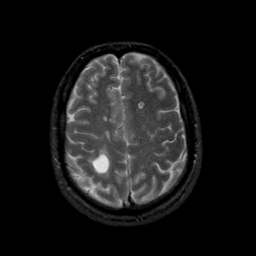

MR Study #9, April 14, 1991 -- Slice #38